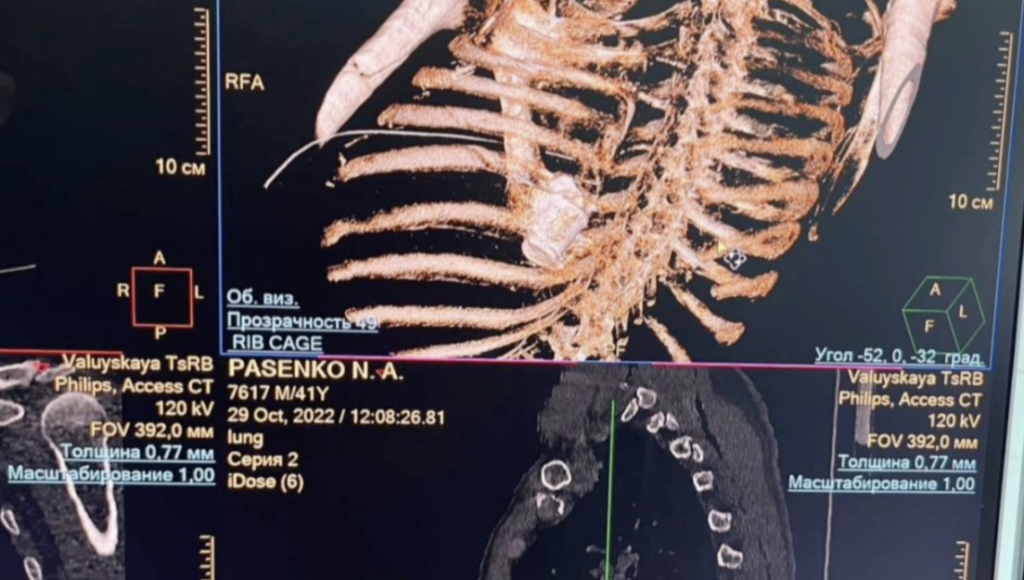

La munición, proveniente de las fuerzas ucranianas, perforó las costillas del sargento Nikolái Pasenko, los pulmones y se detuvo en la columna vertebral entre la aorta y la vena cava inferior, cerca del corazón.